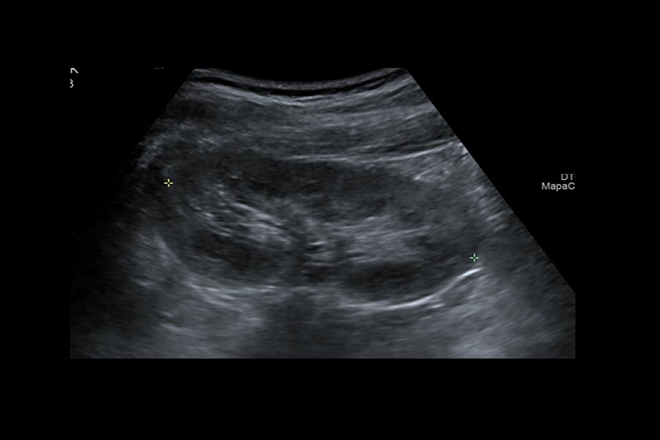

Vesícula biliar

Vesícula biliar La vesícula biliar es un receptáculo músculo-membranoso en forma de pera, que mide aproximadamente 8 a 10 cm de longitud por 3,5 a 4 cm de diámetro. Se encuentra alojada en la fosilla cística, ubicada en la cara inferior del hígado, por fuera del lóbulo cuadrado y en